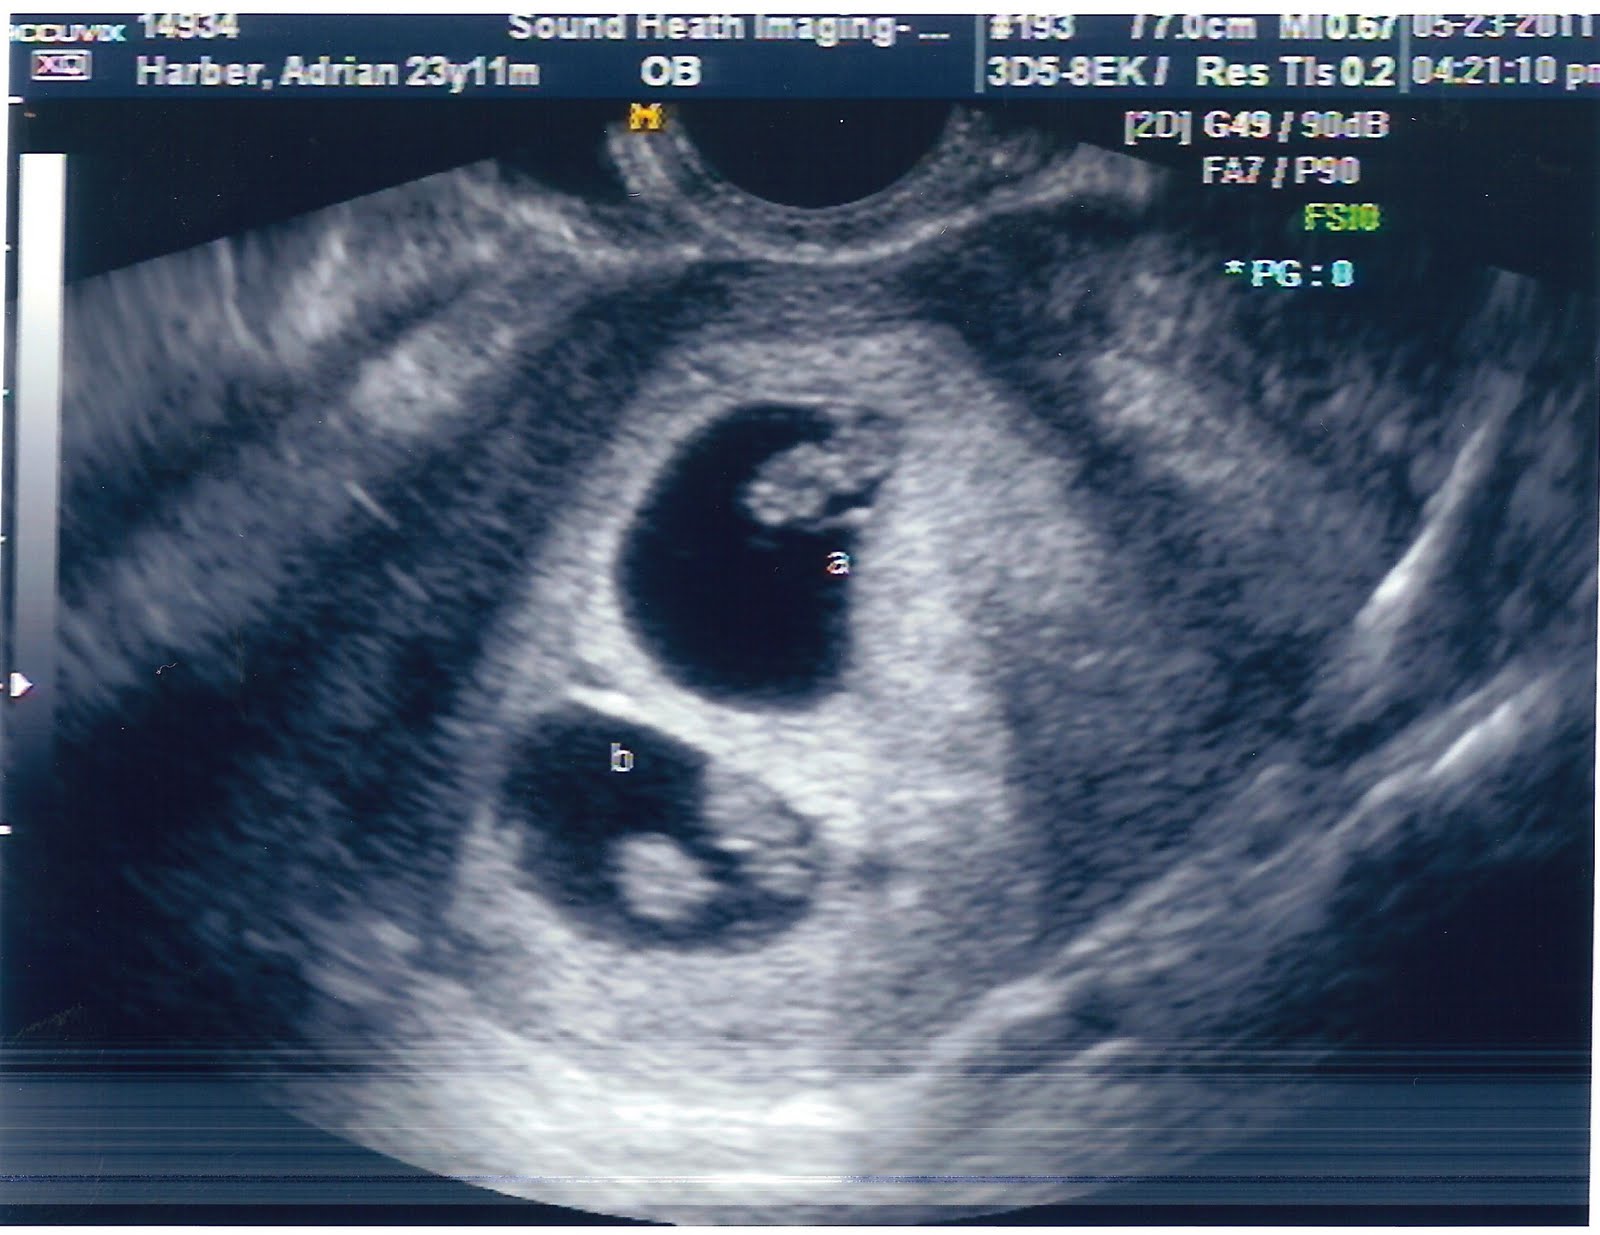

Luke and I went in for an in depth u/s today. I must say, I'm so in love with the little ones. To see their little hearts just beating away melted my heart. The tech moved my due date to Jan. 8th, based off of ovulation. Which is right where the little ones were measuring (7w1d). Not that it really matters, I'm sure they'll make their appearance in Dec. anyway. :) Anyhow here's the little ones!

I know they don't look like babies yet, but I still think they're adorable! :D Baby A's heartbeat was 152 bpm and Baby B was at 164 bpm. :)